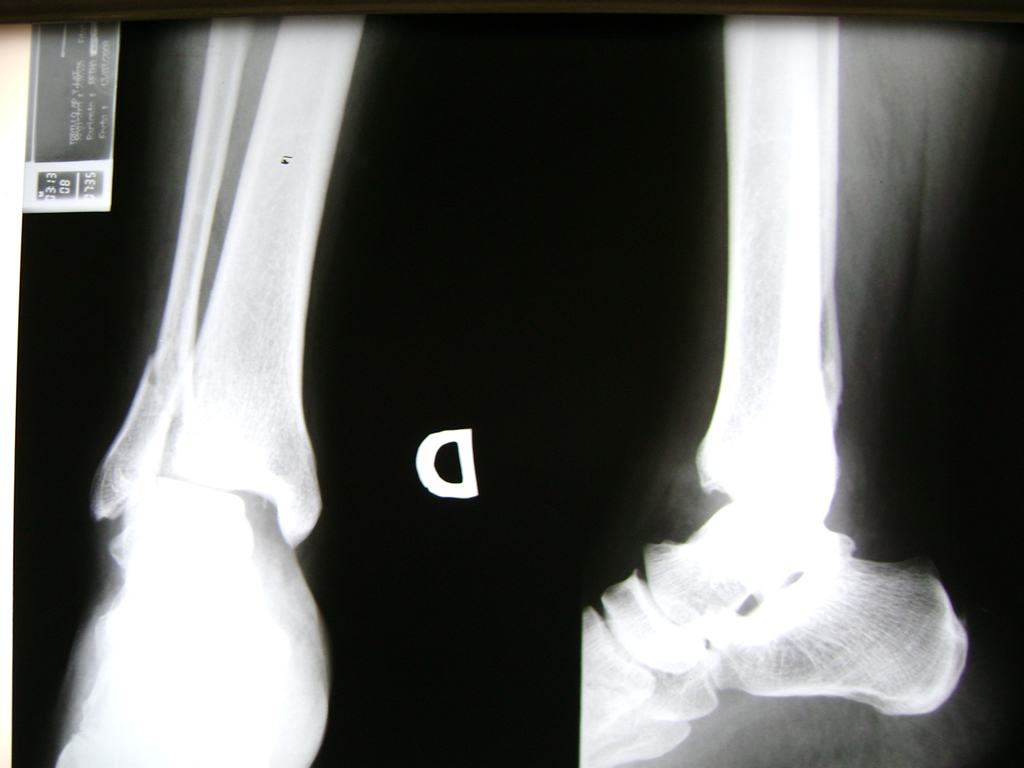

Una fractura de tobillo es la rotura de uno o más de los huesos del tobillo. Estas fracturas pueden ser:

Cuando se necesita cirugía, es probable que esta implique el uso de clavijas de metal, tornillos o placas para sostener los huesos en su lugar mientras la fractura se consolida. Los elementos de soporte pueden ser temporales o permanentes.